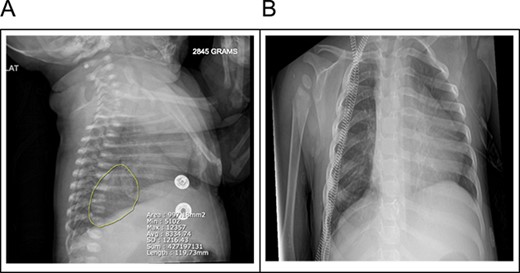

A 20-month female presented with her mother to the pediatric surgery office with a known history of pulmonary sequestration. Imaging at the time of birth revealed a 3.8 × 2.6 × 2.8 cm ovoid hazy opacity projecting in the right hemithorax in the expected location of the right lower lobe (Fig. 1). This was followed up with an MRI confirming a 2.9 × 2.6 cm segment of ELS arterial inflow identified from the celiac trunk (Fig. 2). No emergent surgeries were indicated at that time.

(A) A 3.8 × 2.6 × 2.8 cm ovoid hazy opacity is projecting in the right hemithorax in the expected location of the right lower lobe. (B) Right lower lobe 3.8 cm faintly opaque lesion may represent pulmonary sequestration rather than duplication cyst or other mediastinal lesions.